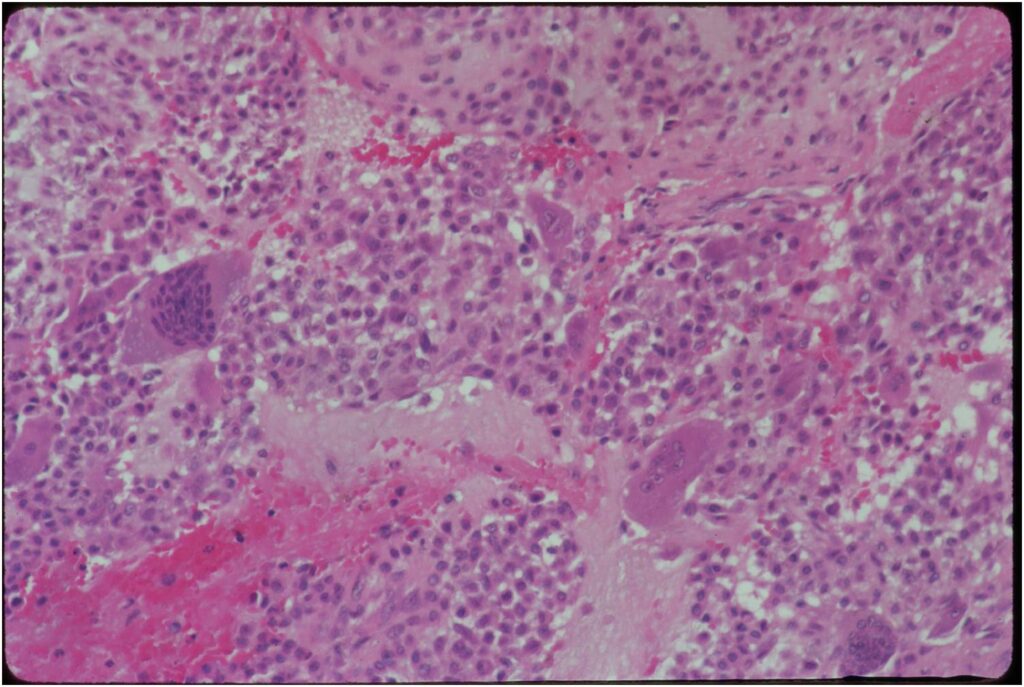

General Information Enchondroma is a benign indolent intramedullary hyaline cartilage neoplasm Accounts for 10% of all benign osseous tumors Limited growth, most lesions are less than 5 cm in maximal dimension Bones grow from a cartilaginous growth plate that...